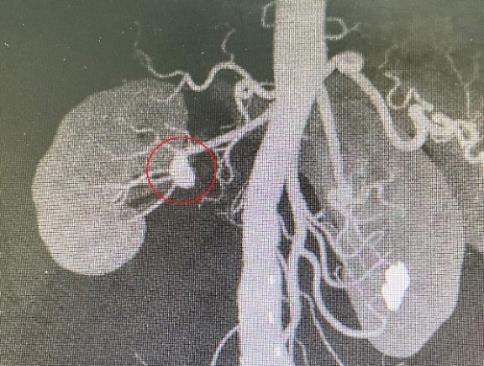

年過(guò)五旬的許老師,稍早前開啟發(fā)掘自身的血壓異樣上升,便去醫(yī)院檢驗(yàn)肌體,無(wú)意中發(fā)掘腎上長(zhǎng)了個(gè)動(dòng)脈瘤。該動(dòng)脈瘤長(zhǎng)的位子有類特殊,在腎動(dòng)脈分叉的地區(qū),累及到了5條腎臟分類動(dòng)脈。

影像檢驗(yàn)發(fā)掘,老許的腎動(dòng)脈瘤已然深入到腎臟內(nèi)部,隨時(shí)有爆裂危害。

由于老許的腎動(dòng)脈瘤較為高難,瘤體乃至已然深入腎臟。手術(shù)隊(duì)伍還借用了超前的3D打印技巧重建了腎動(dòng)脈瘤實(shí)體模型,精確設(shè)計(jì)手術(shù)計(jì)劃,將危害降至最低。